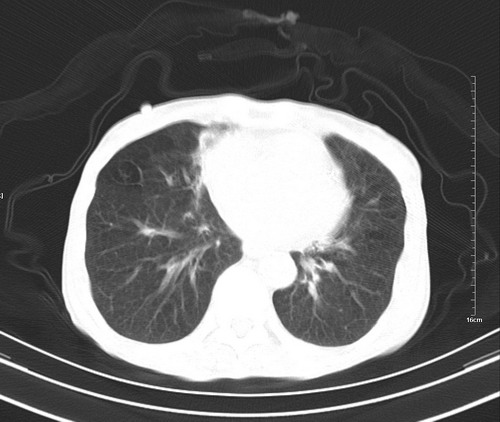

病人,女,79岁,主要因腹疼二月入院,彩超,肝,胆,脾,未见异常,胸透上消化道造影未见异常,化验白细胞增高,内科医生让做胸部ct检查,因为熟人多做了腹部(外科会诊考虑胆囊炎).现ct片如下请假各位战友.

肺癌,纵隔淋巴结转移,肝左叶病变考虑为转移病灶。

后中纵隔团块影,伴气管、食道受压移位,首先考虑转移瘤,肝s5段低密度灶。建议增强检查,另外其结肠是否有问题请提供,右肺部分肺叶局限含气增多,考虑局限肺气肿。

建议强化检查,考虑纵隔型肺癌,小细胞可能性大。